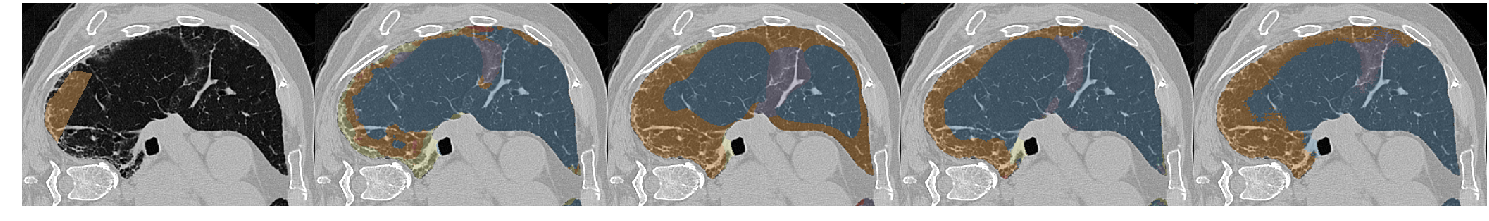

Table III presents a comparison between the proposed network and three previous studies. It has to be noted that all models used the same unsupervised weight (wu=0.1subscript𝑤𝑢0.1w_{u}=0.1) and whenever batch normalization was performed, this was based on batch statistics (instance normalization) since this yielded the best results. Fig. 7 illustrates a few segmentation results for each of the models in Table III.

The first line of the table refers to our previous work [5], which has been converted into a fully convolutional network so it can accept arbitrarily sized images for input. Its low accuracy is probably due to the small receptive field (33×\times33) and the extensive pooling. This architecture was sufficient to describe the local texture of the 32×\times32 single-class patches in [5], but could not capture higher level structure that is present in the whole-lung dataset of this study. The results of the model in Fig. 7 show its noisy output near the lung boundaries or between patterns, where context information could be useful. Segnet [15] and U-net [17] yielded better results, with the latter being slightly faster and substantially more accurate. Both models have a very high number of parameters and large enough receptive fields to capture any relevant information. The superior performance of U-net could be attributed to its skip connections that allow features from the lower scales to directly contribute to its output. Indeed, Fig. 7 illustrates the more detailed results of U-net as opposed to the overly smoothed areas produced by Segnet. Finally, the proposed network yielded the best results, while being faster and having far fewer parameters. The output examples in Fig. 7 indicate that the proposed model manages to keep a better balance between fine details and smooth border among the different classes. Even thought it is really difficult to visually assess the performance of the system for the different classes, there are a few examples in Fig. 7 with wrong classifications on which we can comment. Firstly, parts of the broncho-vascular tree in the third row were recognized as consolidation because of their similar densities, while accentuated terminal bronchial parts, that might be physiological as well, caused the erroneous classification of healthy areas into reticulation, in the first row. Some mistakes however are also attributed in the limited number of annotated classes. For example in row 6, there are emphysematic areas (dark area in the center of the lung) that have been annotated as healthy due to their similar density. Figure 6 shows the confusion matrix of the proposed model. As expected, many of the misclassifications occur between reticulation and honeycombing due to their similar textural appearance. Moreover, healthy tissue is often confused with reticulation probably because of the 2D sections of the bronchovascular tree that could resemble reticular patterns.

Refer to caption

Figure 7: Output examples for the models of Table III. From left to right: Ground Truth, ILD-CNN, Segnet, U-net, Proposed. Each example has a different pattern annotated. From top to bottom: Healthy (Blue), Ground Glass Opacity (Purple), Micronodules (Green), Consolidation (Yellow), Reticulation (Orange) and Honeycombing (Red).